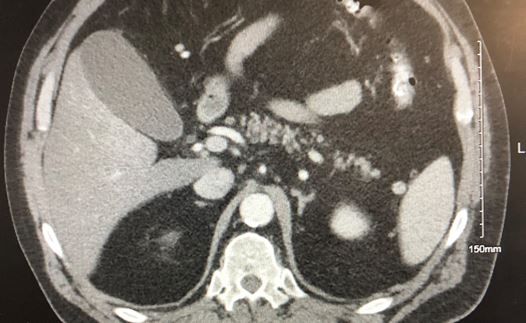

A man in his mid-sixties reports constant bilateral chest pain that radiates to the back that began yesterday. Can you Dx based on the CT image here?

History of present illness. A man in his mid-sixties with a history of endoscopy-confirmed gastroesophageal reflux disease (GERD) and esophagitis presents to the emergency department with epigastric/chest pain. He reports constant bilateral chest pain radiating to the back since the day before. He denies any aggravating factors, shortness of breath, nausea, or vomiting. He took Pepto-Bismol with minimal relief.

Vital signs & physical examination. Vital signs are normal except for elevated blood pressure (190/115 mm Hg). Other than mild epigastric tenderness, the physical examination is otherwise unremarkable.

Imaging: see CT below